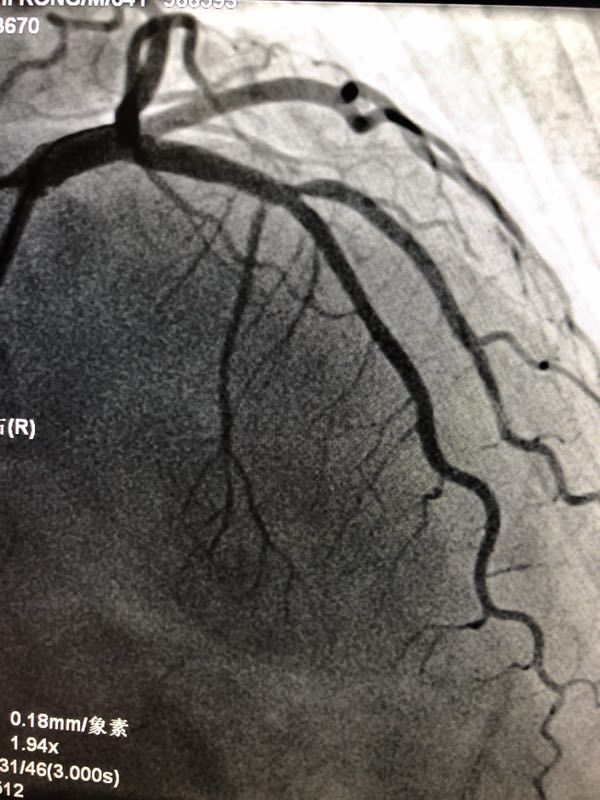

重庆医科大学附属第二医院心内科殷跃辉教授团队陈国柱副主任医师今日成功实施重庆首例 “生物可吸收心脏支架”植入术。在殷跃辉主任指导、